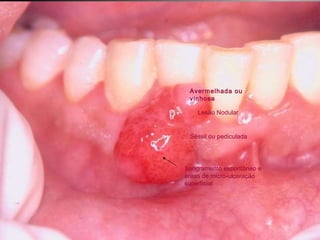

25 -  L.C.S., sexo masculino, 18 anos de idade, se apresentou com queixa de aumento de volume na gengiva entre os dentes 23  e  24.  Pelo  exame  clínico,  constatamos  a  presença  de  um  nódulo  séssil,  de  contornos  irregulares,  coloração  avermelhada, com sangramento abundante ao mínimo toque e evolução de 1 ano. O paciente apresentava higiene bucal precária com presença de placa bacteriana e tártaro. Com base no quadro clínico, o diagnóstico é: a) Fibroma e granuloma piogênico. b) Granuloma piogênico e hiperplasia fibrosa inflamatória. c) Lesão periférica (granuloma) de células gigantes e fibroma. d) Granuloma piogênico e lesão periférica (granuloma) de células gigantes. e) Hiperplasia fibrosa inflamatória e fibroma.

Granuloma Piogênico Lesão Nodular Séssil ou pediculada Avermelhada ou vinhosa Sangramento espontâneo e áreas de micro-ulceração superficial

Granuloma Piogênico Lesões nodulares de coloração avermelhada ou vinhosa Provavelmente uma reação inflamatória exagerada ao trauma menor Crescimento rápido, às vezes sangramento espontâneo Ocorre em qualquer idade mas parece mais freqüente em adultos jovens e adolescentes  Localização mais comum: gengiva (NEVILLE,2001)

Granuloma Piogênico Lesões mais antigas, são menos vasculares e mais fibrosas Papila interdental e regiões anteriores são áreas preferenciais, principalmente por vestibular (BORK,1996)

Granuloma Piogênico LesãoNodular Séssil ou pediculada Avermelhada ou vinhosa Sangramento espontâneo e áreas de micro-ulceração superficial

Granuloma Piogênico Lesõesnodulares de coloração avermelhada ou vinhosa Provavelmente uma reação inflamatória exagerada ao trauma menor Crescimento rápido, às vezes sangramento espontâneo Ocorre em qualquer idade mas parece mais freqüente em adultos jovens e adolescentes Localização mais comum: gengiva (NEVILLE,2001)

Granuloma Piogênico Lesõesmais antigas, são menos vasculares e mais fibrosas Papila interdental e regiões anteriores são áreas preferenciais, principalmente por vestibular (BORK,1996)